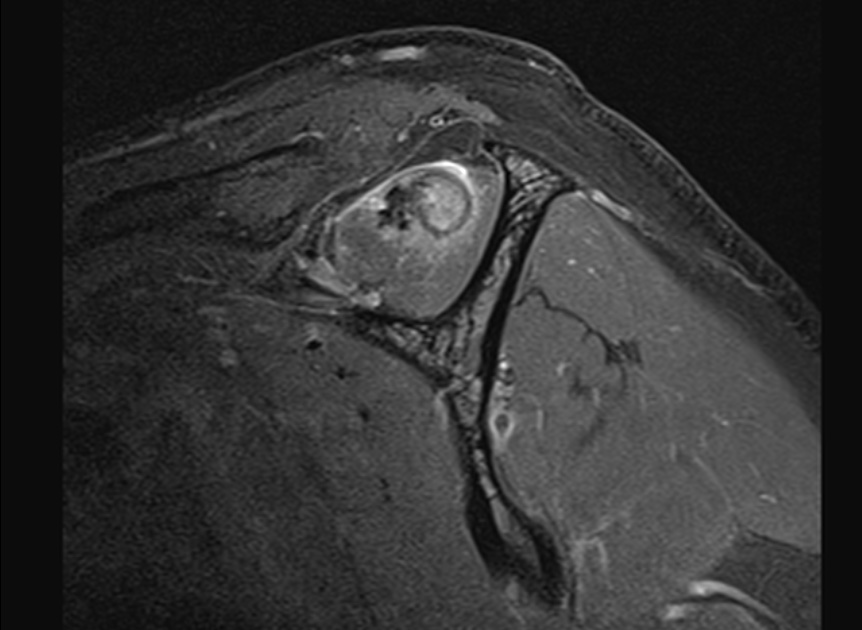

The surgeon said the tear wasnt visible from the articular side and debridement was necessary to reach it from the bursa. The tendon was stuck down and a side to side repair was necessary. You can make out the central defect in the footprint with intact articular and burial surfaces.

I have seen a few of these in Infraspinatus, as per the article linked below, but this was my first in Supraspinatus. Reference article.

Massive interstitial delamination of Supraspinatus with retraction